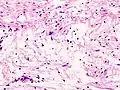

Neurinome subcutané_Antoni_B.jpg.webp)

C'est un sous-type exceptionnel des schwannomes. Il s'agit d'une tumeur nerveuse bénigne, dont le point de départ est la gaine de Schwann. C'est souvent un nodule solitaire, asymptomatique, siégeant dans le tissu cutané ou sous-cutané, et dont la taille augmente progressivement.